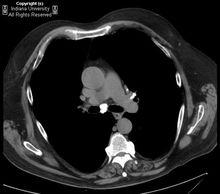

房間隔脂肪瘤樣肥厚CT:均勻的脂肪低密度在房間隔兩側呈啞鈴型表現。可能有多於正常的縱隔、心外膜脂肪含量。心房內脂肪腫塊可與心外膜脂肪相連。